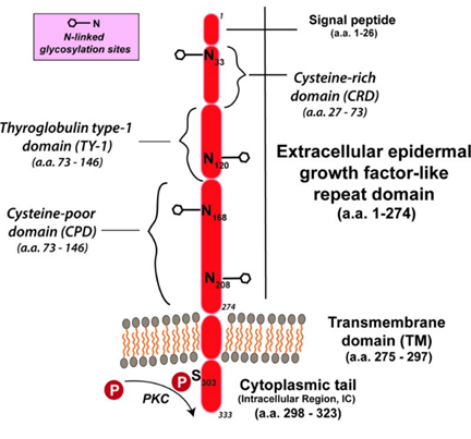

TROP2蛋白结构及功能特点

TROP2是一种跨膜糖蛋白,如图1所示由胞外结构域、跨膜结构域、胞内结构域三部分构成,最初被认为是识别滋养层细胞的标志物,进一步研究证实其在多种实体瘤中过表达,并通过多种信号通路调控肿瘤的生长、侵袭和扩散。

TROP2蛋白结构示意图